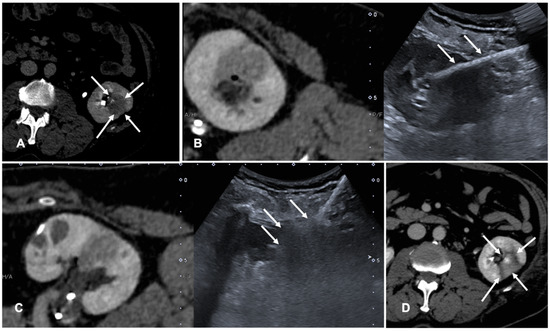

Figure 3. Case of a patient with left kidney clear cell renal cancer treated with microwave ablation (MWA). (A) Axial view during delayed excretory phase of the preoperative contrast enhanced Computed Tomography (CECT) showing a 25 mm intrarenal lesion (white arrows); (B) Fusion imaging (FI) of the same CT (left side) and intraoperative ultrasound (right side). MWA needle is marked by two solid arrows on the right. (C) FI during MWA of the lesion. Arrows point out the area of gas formation at the tip of the ablation needle. (D) An axial view of the control CT at the end of the procedure. Arrows point out the resulting completely ablated area of the kidney lesion.

FI is used to co-register previous CT or CBCT and real-time US to perform tumor ablations. Assisted CBCT and US FI are effective, safe and feasible in TA, but only a few papers investigated the advantages and limitations of these techniques [35,36,37]. A case of a patient with renal tumor treated with the guidance of FI is shown in Figure 3.